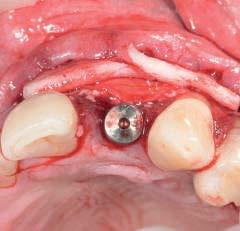

Case photograph and x-ray source Peter Kobolt; Index BPTS by Peter Kobolt; fig. 1 Medimpex, Advan

All procedures were made in outpatient clinic Humanikdent d.o.o., Smrecnikovo 20, 2392 Mezica, SLO, EU